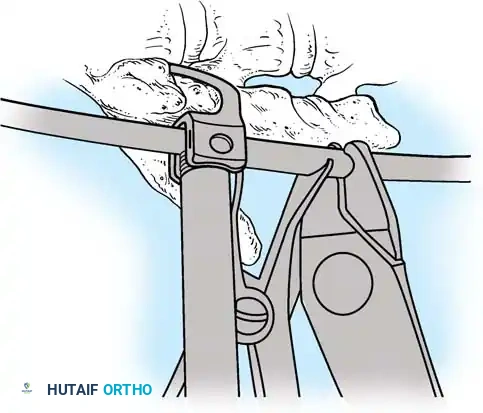

The Hall Technique

The Hall technique offers an alternative method for facet obliteration and grafting, particularly useful in rigid deformities.

Fig. 38-28: The Hall technique of facet fusion, involving sharp excision of the inferior facet and trough creation.

- Sharply amputate the inferior articular facet with a gouge and remove the bone fragment entirely. This exposes the cartilage of the superior facet.

- Remove the exposed cartilage completely with a sharp curet.

- Create a bleeding trough by removing the outer cortex of the superior facet.

- Impact cancellous bone grafts directly into this vascularized trough.

- Complete the procedure with global decortication of the posterior elements.